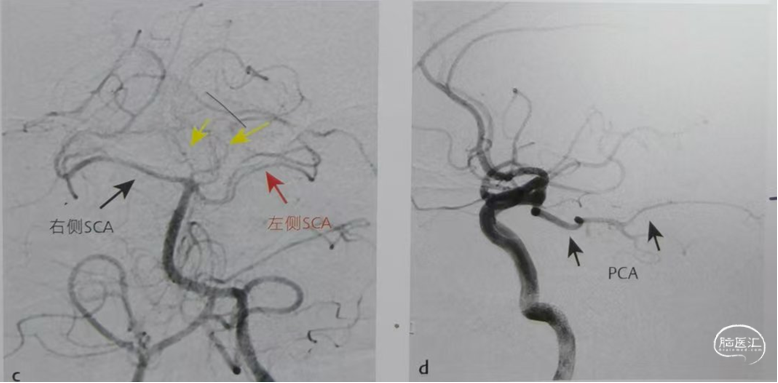

左侧椎动脉造影显示双侧PCA均未显影,双侧小脑上动脉(SCA)显影清晰和丘脑穿支动脉(黄色箭头)可见造影剂充盈。左侧颈内动脉造影同侧大脑后动脉显影(箭头)。丘脑梗塞为颈内动脉发出后交通远端供血血管梗塞。

特别注意:不要将P1段胚胎型缺如或发育不良误判为P1段急性闭塞。不适合进行取栓。